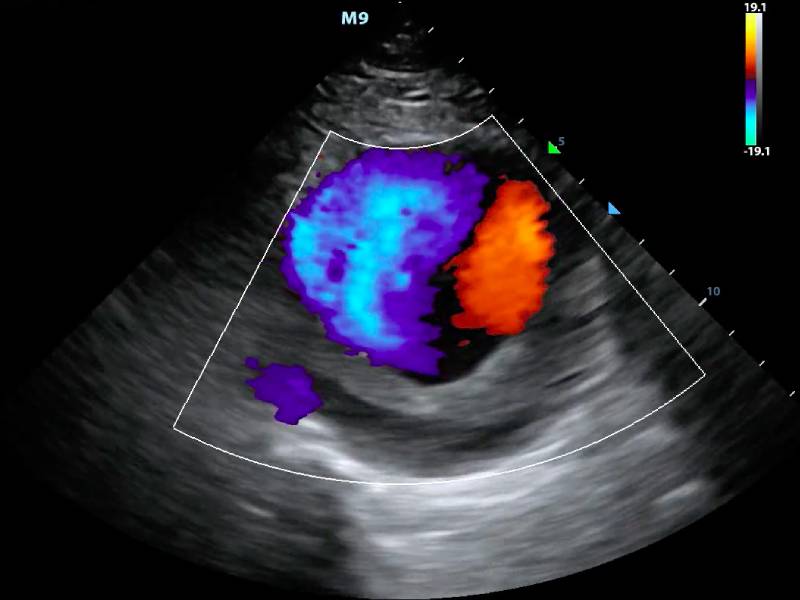

A Colour Doppler Scan is a non-invasive test that uses sound waves to visualize blood flow through arteries and veins. This advanced imaging technique allows doctors to detect blockages, clots, and other vascular issues with high precision. For Rajesh, this scan provided a clear, detailed picture of his circulatory system, revealing a significant blockage in one of his major arteries. The clarity and accuracy of the results were astonishing.

For Rajesh, the Colour Doppler Scan was more than a diagnostic tool; it was a beacon of hope. Understanding the root cause of his pain allowed him and his medical team to create an effective treatment plan. The emotional relief of knowing what was wrong and having a clear path to recovery was immense. Rajesh's experience underscores the critical importance of accurate diagnosis in managing and treating health conditions.

Consider the story of Meena, a 45-year-old school teacher from Mumbai. Like Rajesh, Meena suffered from unexplained leg pain and fatigue. She spent months going from one specialist to another with no clear answers. Finally, a visit to Tushar Diagnostic for a Colour Doppler Scan revealed a deep vein thrombosis (DVT), a potentially life-threatening condition if left untreated. The timely diagnosis allowed Meena to receive the necessary treatment, preventing severe complications and enabling her to return to her beloved teaching career.

The Colour Doppler Scan at Tushar Diagnostic is more than just a medical test; it's a lifeline for individuals like Rajesh and Meena. Its ability to provide precise and timely diagnoses not only alleviates physical pain but also offers emotional solace to patients and their families. If you or someone you love is experiencing similar symptoms, don't wait. Take the first step towards healing and peace of mind.